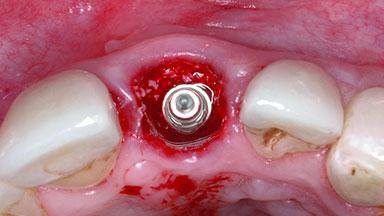

A healthy 23-year-old female patient was referred for a consultation on replacing tooth 21 with an implant-supported restoration. The patient had recently moved to the area and reported a history of endodontic and periodontal treatment for tooth 21. The tooth had been deemed non-restorable by her previous periodontist but since she was going to be moving, he recommended consulting to a dentist in her new city to continue her treatment. A review of her medical history yielded no significant findings and no known drug allergies. The analysis of her smile revealed a medium to high symmetrical smile line and a slightly discolored tooth 21.